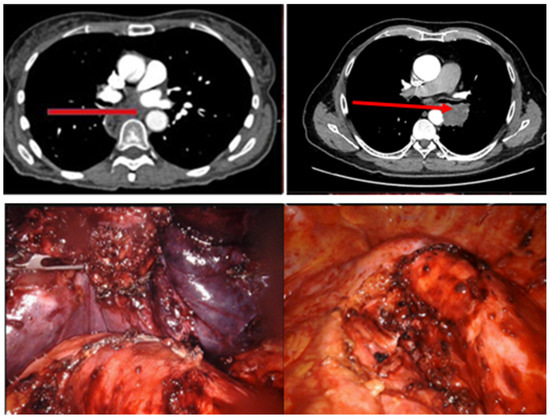

| Case | Tumor | T | N | M | Surgery |

|---|---|---|---|---|---|

| 1 | Metastases | NA | NA | NA | Extrapleural pneumonectomy and pericardial resection |

| 2 | Pleural mesothelioma | 4 | 1 | 0 | Pleurectomy, lower lobe wedge resection |

| 3 | NSCLC (squamous cell carcinoma) | 4 | 0 | 0 | Extrapleural pneumonectomy and pericardial resection |

| 4 | NSCLC (adenocarcinoma) | 1 | 2 | 0 | Parital tumordebulking and para-aortic resection |

| 5 | Malignant peripheral nerve sheath tumor | NA | NA | NA | Para-aortic tumor resection |

| 6 | Esophageal cancer | 4 | 1 | 0 | No surgery |

| 7 | NSCLC (squamous cell carcinoma) | 4 | 2 | 1 | Left lower lobe lobectomy and para-aortic resection |

| 8 | Metastasis | NA | NA | NA | Extrapleural pneumonectomy and para-aortic and diaphragm resection |

| 9 | NSCLC (adenocarcinoma) | 3 | 0 | 1 | Left lower lobe lobectomy |

| 10 | Esophageal carcinoma | 4 | 1 | 0 | Left lower lobe lobectomy and esophagectomy |

| 11 | Esophageal carcinoma | 3 | 1 | 0 | Lymph node resection in the tracheobronchial angle |

| 12 | Esophageal carcinoma | 3 | 1 | 0 | Para-aortic tumor resection |

| 13 | Thymus carcinoma | 3 | 0 | 0 | Mediastinal tumor resection, wedge resection left lower and upper lobe followed by completion lobectomy left upper lobe, pericardial resection, |

| 14 | NSCLC (squamous cell carcinoma) | 2 | 2 | 0 | Completion pneumonectomy left |

| 15 | NSCLC (adenocarcinoma) | 4 | 0 | 1 | Left upper lobe lobectomy |